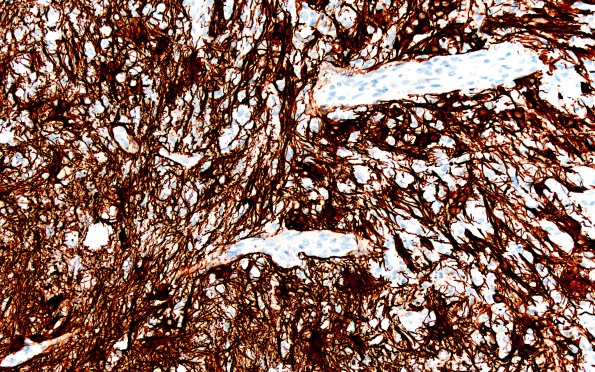

Washington University Experience | MYELIN (IMMUNE-MEDIATED) | Inflammatory Demyelination | 15H2 Inflamm Demyel (Case 15) GFAP 2X

Reactive astrocytic proliferation is seen in both the demyelinated and myelin preserved regions. (GFAP IHC)